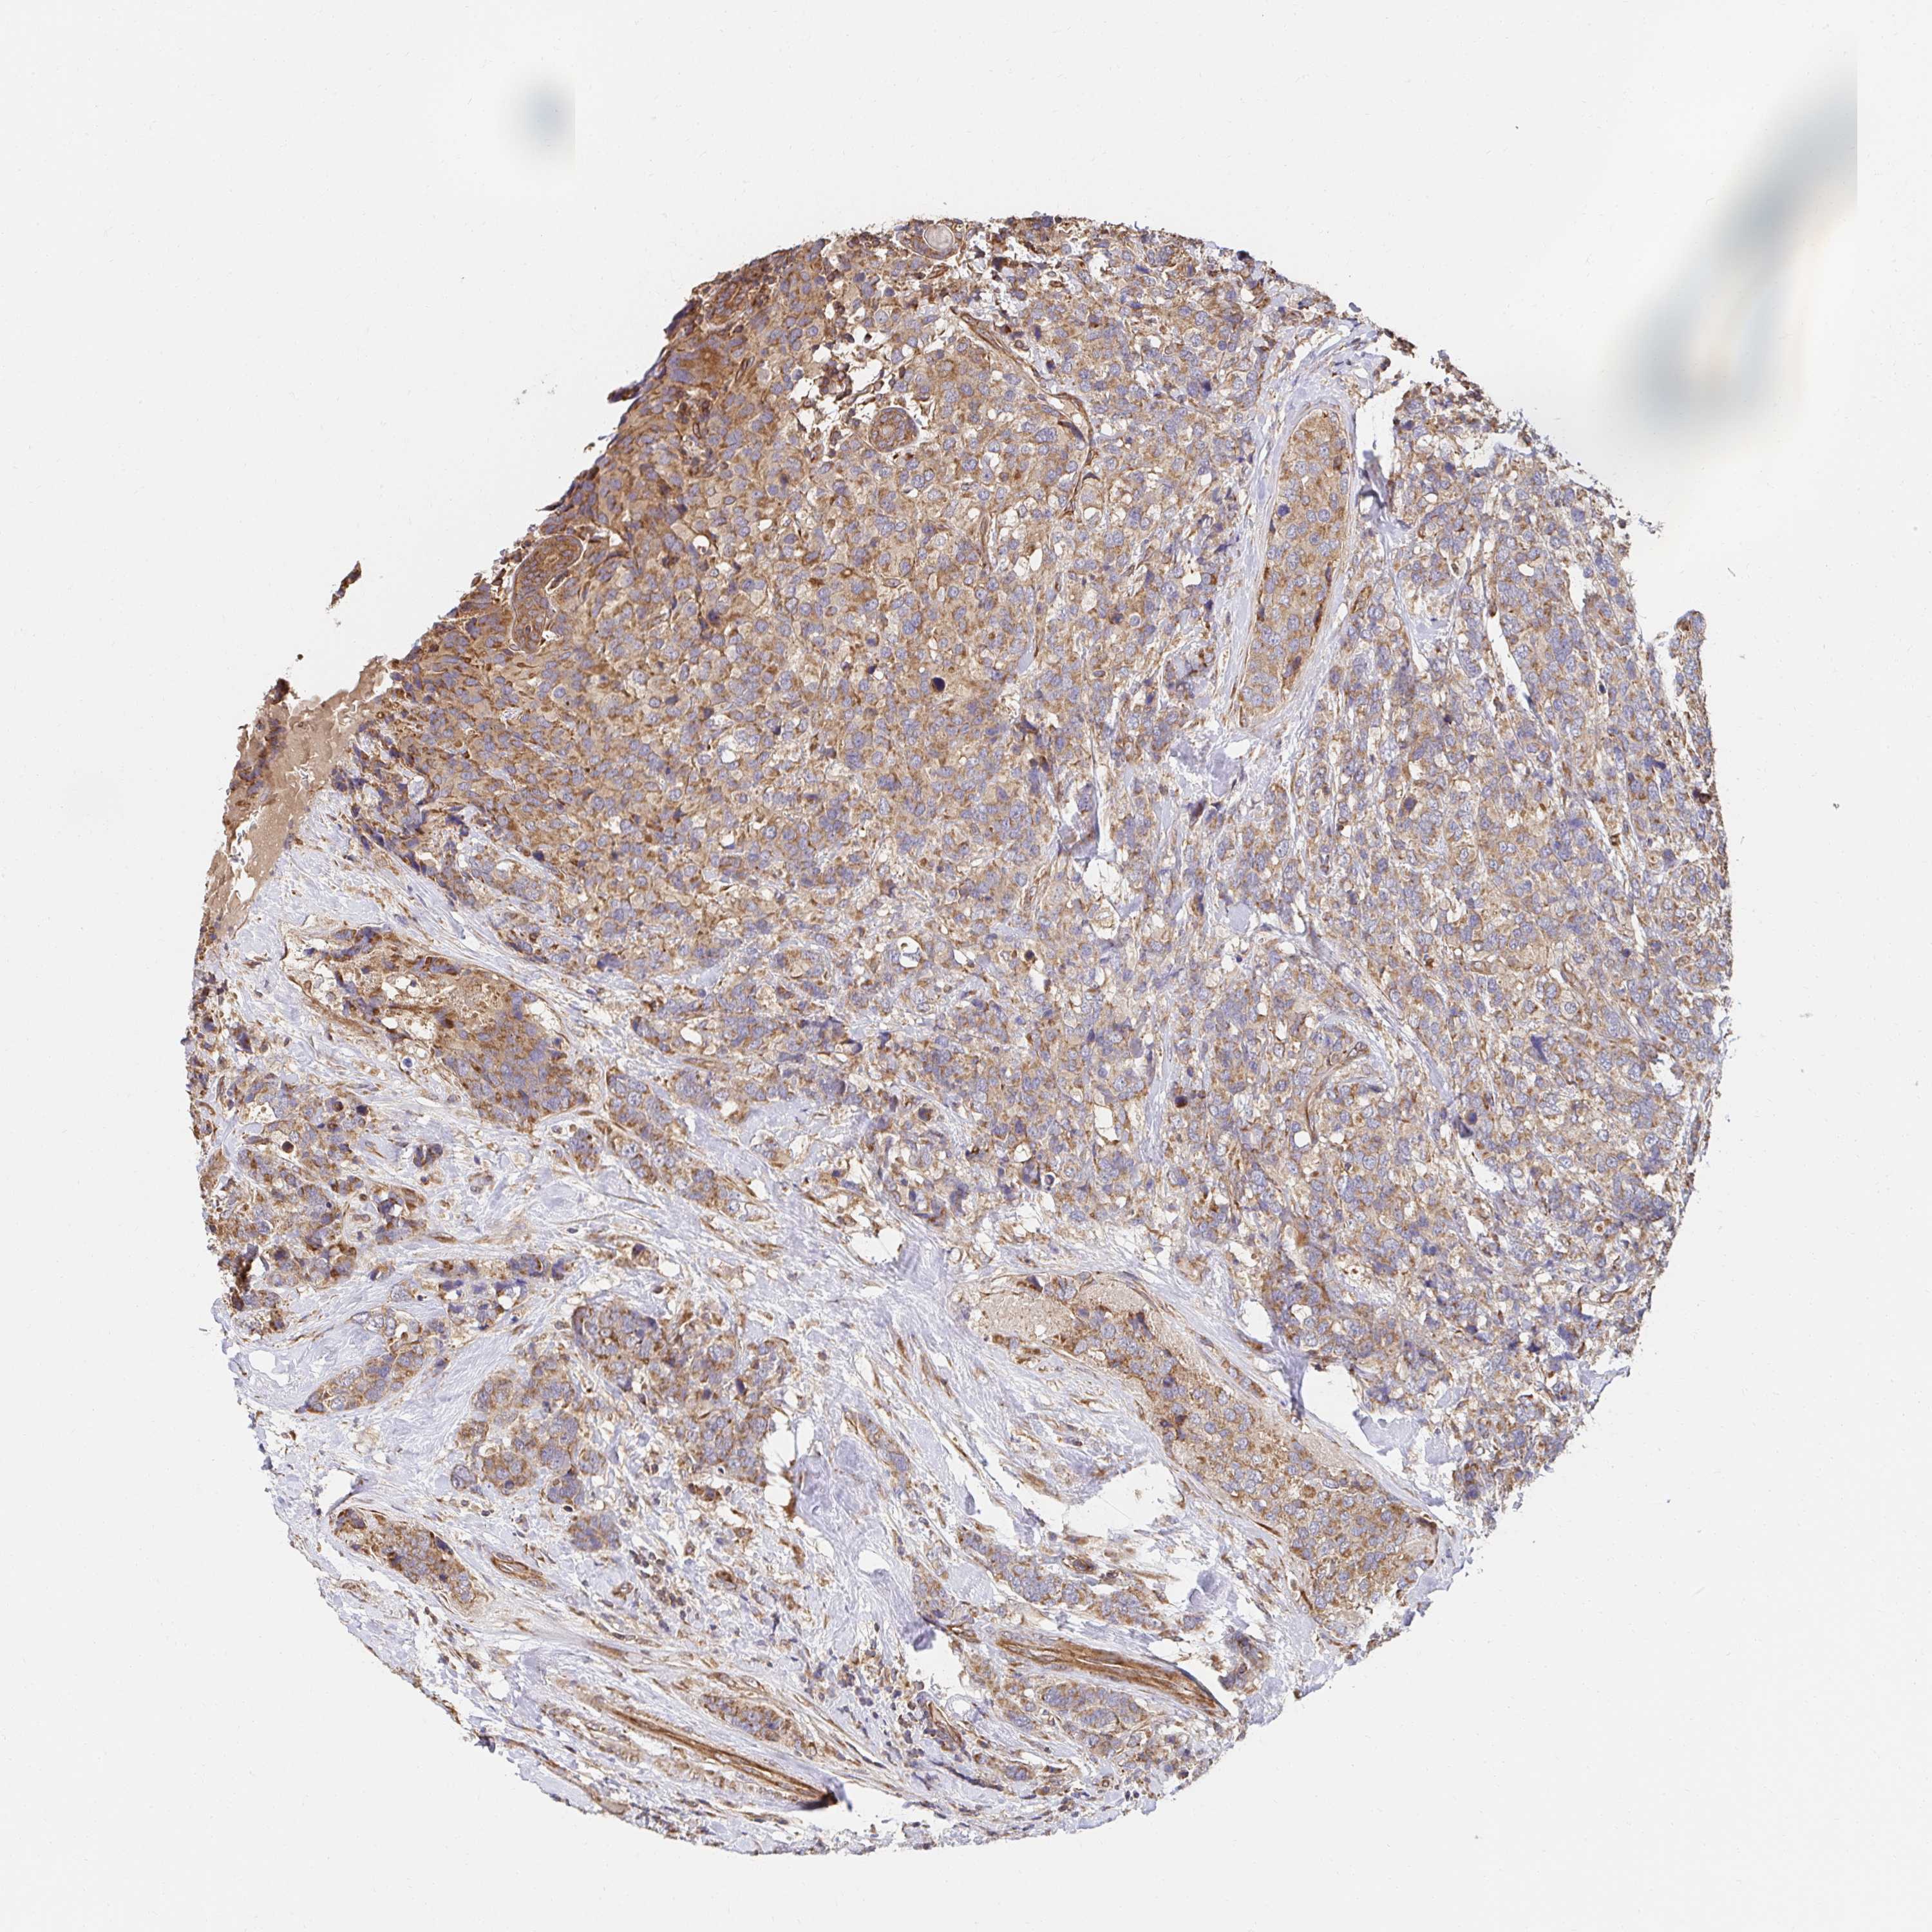

CANCER BREAST CANCER Show tissue menu

Breast cancer

Human cancer